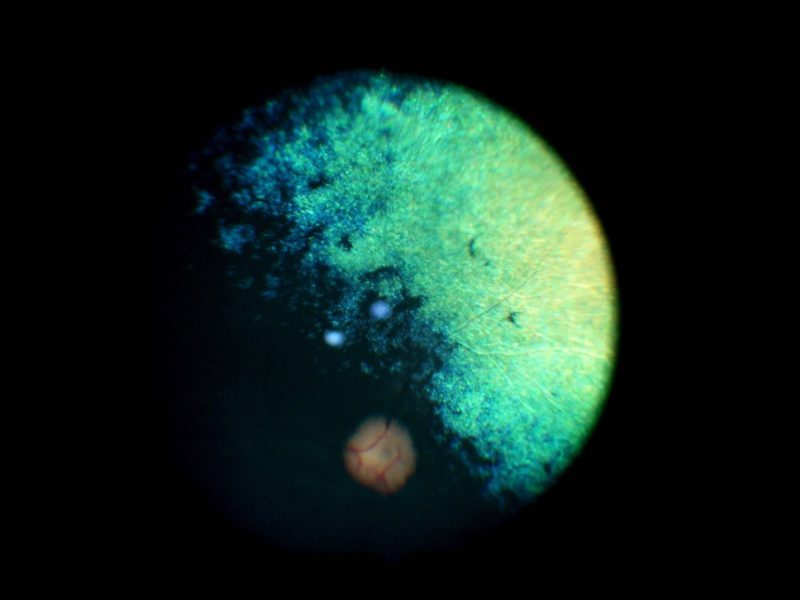

Bei der klassischen PRA beginnen die „Stäbchen“ die für das Nachtsehen zuständig zuerst zu degenerieren bzw. abzusterben. Dieser Vorgang ist nicht schmerzhaft. Im Anfangsstadium ist auffällig, dass sich die Tiere im Dämmerlicht oder im Dunkeln unsicher bewegen, ängstlich sind und unbekannte Objekte oder Personen verbellen. Teilweise stoßen die Tiere auch gegen ihnen unbekannte Dinge an oder weichen dem Besitzer nicht mehr von der Seite. Ein weiteres Zeichen ist der unvollständige Schluss der Pupillen bei einfallendem Licht und ein stärkeres “Leuchten” der Augen in der Dunkelheit als gewöhnlich, was ein Zeichen für eine dünner werdende Netzhaut ist. Dadurch kommt die unter der Netzhaut gelegene Schicht, das leuchtende Tapetum lucidum, verstärkt zum Vorschein. Diese Symptome verschlechtern sich dann in den darauffolgenden Monaten bis Jahren und führen zu einer spürbaren Sehverschlechterung auch im hellen Licht, da dann auch die „Zapfen“ beginnen zu degenerieren. Auch dieser Vorgang ist nicht schmerzhaft. Zwischen den ersten Symptomen und der vollständigen Erblindung vergehen in der Regel 3-6 Jahre.  Selten gibt es PRA Formen, bei welchen zuerst die Zapfen und im Anschluss daran die Stäbchen degenerieren. Dann tritt genau der umgekehrte Fall ein und die Tiere erblinden zuerst bei hellem Licht und anschließend auch bei Dunkelheit, dies sind Sonderformen und enden leider auch immer mit der vollständigen Erblindung des Tieres. Eine häufige Folgeerkrankung der PRA stellt der graue Star (Katarakt oder Eintrübung der Linse) dar. Als Folge des grauen Stars kann nach einigen Jahren der grüne Star (Erhöhung des Augeninnendrucks) auftreten. Der grüne Star gehört mit zu den schmerzhaftesten Erkrankungen des Auges und kann zum Verlust des gesamten Augapfels führen. Aus diesem Grunde sollten Tiere, die an der PRA erkranken, ca. einmal jährlich zu einer Kontrolluntersuchung der Augen vorgestellt werden, damit weitere Folgeschäden frühzeitig erkannt und dann behandelt werden können, um schmerzhafte Zustände zu vermeiden.